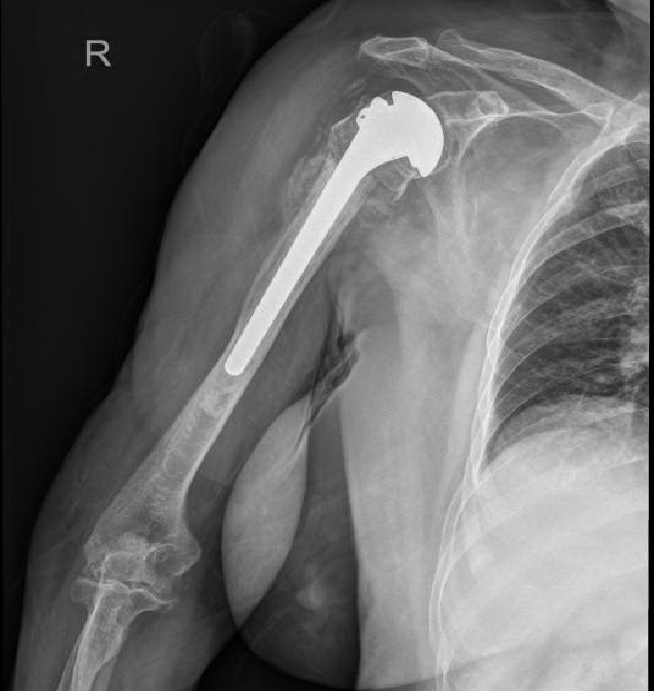

1、右肱骨近端骨折(Neer 4部分)

综合患者耐受及依从性、骨折类型及粉碎程度、骨量情况、重建后稳定性及康复等因素,决定行右人工肱骨头置换术(半肩置换)及左桡骨远端骨折切复内固定术。

1、行右人工肱骨头置换术(半肩置换),术后影像学检查